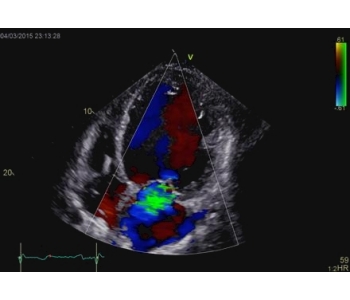

The 4D ICE NUVISION Catheter offers real-time volumetric imaging, a 90x90 field of view, 4D color Doppler flow capabilities, and an independently rotating tip, making it an ideal choice for left atrial appendage closure (LAAC) procedures.